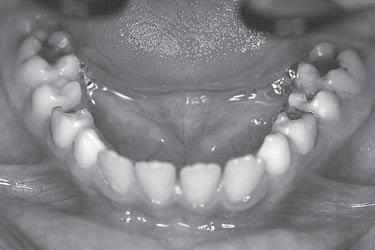

Jsem stále více přesvědčena o tom, že informaci o přítomnosti ortodontické anomálie, která se plně projeví až za několik let, máme k dispozici velmi brzy. Určitá podezření můžeme vyslovit obvykle už při zahájení první fáze výměny chrupu. Jen je třeba dobře se dívat a věnovat pozornost nenápadným symptomům, které na ni upozorňují. Jinak se budeme neustále setkávat s udivenými dospělými pacienty s retinovanými špičáky, s perzistujícími dočasnými zuby a s pacienty, jejichž chrup nelze kvůli ortodontické anomálii dobře ošetřovat.